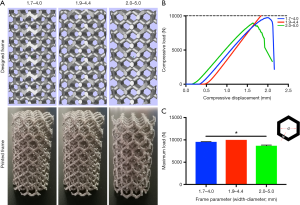

Parameter optimization and mechanical strength verification for the 3D-printed Ti6Al4V frame

A cylindrical testing frame (2.5 cm diameter × 5 cm height) with a basic regular hexagon unit was designed by using Mimics software (Materialise, Belgium). The width of this hexagon’s sides (w) and the diameter of the circle inscribed in it (d) were used as the adjustable parameters. Three different combinations of this width and diameter, namely (w=1.7 mm, d=4.0 mm), (w=1.9 mm, d=4.4 mm), and (w=2.0 mm, d=5.0 mm), were used to fabricate the cylindrical Ti6Al4V testing frames by using electron beam melting (EBM) (Figure 2A). A mechanical testing machine (Instron 8874; Instron, USA) was used to perform compression tests to compare the three frames’ mechanical properties (Figure 2B,C). Briefly, the compression tool was connected to the machine, and the load was applied to the testing frame until the frame collapsed. The parameter combination with the best mechanical performance was used to prepare the animal model’s frames.

Optimization of printing parameters and the preparation of the repair frames

The cylindrical testing frame’s design parameters with regular hexagonal basic structural units were optimized, and then the test frames were made with Ti6Al4V. Three columnar frames with different combinations of width (w) and the inscribed circle diameter (d) of the regular hexagonal unit were prepared: w=1.7 mm, d=4.0 mm; w=1.9 mm, d=4.4 mm and w=2.0 mm, d=5.0 mm. The frame with parameters of w=1.9 mm, d=4.4 mm did not collapse when the load reached 10,000 N, whereas the other two were destroyed before the load reached 10,000 N (Figure 2B). Specifically, the maximum load was 9,553.7±51.9 N for the frame with w=1.7 mm, d=4.0 mm; 8,693.6±146.9 N for the frame with w=2.0 mm d=5.0 mm and >10,000 N for the frame with w=1.9 mm, d=4.4 mm; the maximum load was significantly higher for the frame with the latter combination than those for the frames with the other two-parameter combinations (P<0.05) (Figure 2C).

To select the appropriate printing parameters to ensure the mechanical strength of the frame, we evaluated the mechanical properties of the cylindrical frame with three sets of parameters according to the mechanical test standard (18). Inspired by a honeycomb, in which each comb is connected to other combs on all six sides and achieves good space utilization with less material, we used a regular hexagonal basic printing unit. The width of the side and the diameter of the hexagonal units’ inscribed circle are the two key factors that affect the overall mechanical properties of the frame. Theoretically, a larger inscribed circle diameter provides more space for a bone filling but reduces the mechanical strength, whereas the opposite relationship is observed for the side’s width. In this study, the frame with the combination of w=1.9 mm and d=4.4 mm for the hexagonal units had a better mechanical performance, indicating that the mechanical increment caused by the increase in the side width from 1.7 to 1.9 mm exceeded the mechanical decrement caused by the increase in the inscribed circle diameter from 4.0 to 4.4 mm.

Additionally, the mechanical increase by increasing the side width from 1.9 mm to 2.0 mm did not exceed the mechanical decrease by increasing the inscribed circle diameter from 4.4 to 5.0 mm. Consequently, we used the optimal width and diameter parameters to prepare the Ti6Al4V frame, which matched the goat’s distal femur’s lateral half. The corresponding internal fixation system was designed and fabricated at the same time. Since the defect model involved the articular surface, a PCL film was used to cover the frame’s distal end to improve smoothness and reduce rigidity to minimize potential joint damage. Also, a Bio-Gide collagen membrane was sutured into the PCL film’s surface to protect the joints further.